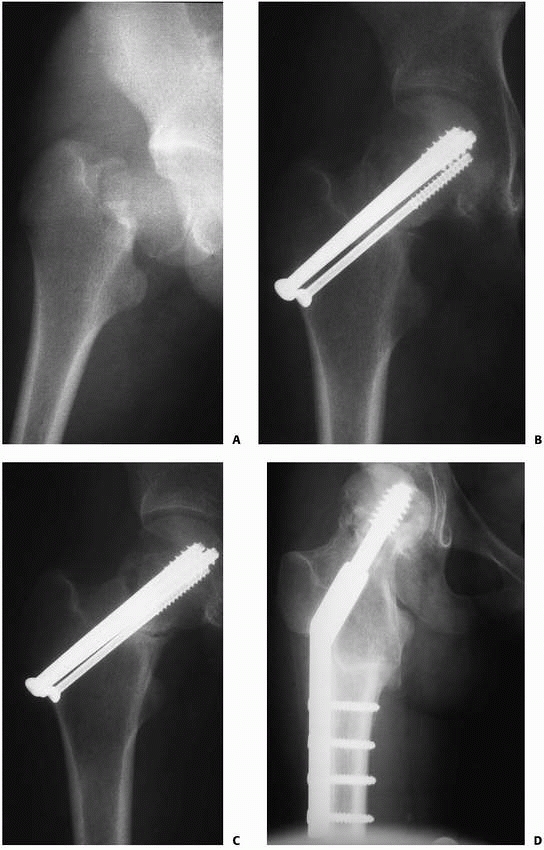

| FIGURE 21-17 A. A 15-year-old girl with a markedly displaced type II femoral neck fracture. B. She underwent open reduction and internal fixation with two 7.3-mm cannulated screws and one 4.5-mm cannulated screw. Primary bone grafting of a large defect in the superior neck was also performed. C. Radiograph at 5 months showing a persistent fracture line D. Six weeks after valgus intertrochanteric osteotomy. The fracture is healing. |

The compression type appears as reactive bone formation on the inferior